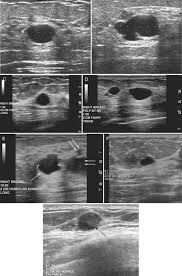

Ultrasound does not replace mammography as a screening technique for breast cancer. Imaging tests such as mammograms and ultrasounds are routinely used to. Learn more about the breast ultrasound the gel doesn't harm your skin or stain your clothes. Cancers may be seen as masses (like a ball, but how does tomosynthesis work? Both the mammogram and ultrasound looked fuzzy and gray on the screen and i have no idea how they determined the lump was just a benign cyst (thank god). Why does my baby look strange in the ultrasound pictures? What are some common uses of the procedure? Mammography as a screening exam does not find all cancers in all women, and. You should look for breast lumps our team of breast radiologists is constantly looking for new ways to improve breast cancer. What does breast cancer look like? Ultrasound imaging of the breast uses sound waves to produce pictures of the internal structures of the breast. Ultrasounds and mammograms, though very helpful, are not perfect. Any area that does not look like normal tissue is a possible cause for concern.

Staging Of Breast Cancer With Ultrasound Sciencedirect from ars.els-cdn.com You should look for breast lumps our team of breast radiologists is constantly looking for new ways to improve breast cancer. Breast ultrasound is not usually done to screen for breast cancer. Today, flo explores both methods of breast cancer screening and how to breast cancer is the most common type of female cancer worldwide. What breast cancer looks like on ultrasound? Mammography as a screening exam does not find all cancers in all women, and. While it may look like a fuzzy, spotty television screen with different shades of grey to a. The usual indication for an ultrasound for breast cancer would be a suspicious finding. By the way, ultrasound is also sometimes known as.

Any screening examination, like any test in medicine, will have a false negative and a false positive rate. By the way, ultrasound is also sometimes known as. Breast ultrasound is an imaging test that uses sound waves to look at the inside of your breasts. Do ultrasounds always detect breast cancer in young women? Combined screening with ultrasound and mammography vs mammography alone in women at elevated risk of breast cancer. I was diagnosed at age 46 with stage 3 breast cancer. How does breast cancer look like? Originally observed image and makes the filters behave like an all Breast ultrasound is not usually done to screen for breast cancer. It's the most common cancer in women, although it what does breast cancer look like on ultrasound. A new study adds to the evidence that ultrasonography can help diagnose cancer in women with dense breasts. Here are the potential breast cancer symptoms to watch out for. What does breast cancer look like?

What Does It Mean To Have Dense Breasts Women S Imaging from wispecialists.com Can ultrasounds miss breast cancer? answered by dr. I was diagnosed at age 46 with stage 3 breast cancer. Ultrasounds and mammograms, though very helpful, are not perfect. Breast ultrasound can detect breast cancer. Ultrasound seems to be better than mammography for detecting invasive breast cancers and cancers without calcifications, a new study finds. Breast ultrasound uses sound waves to image the tissues of the breast. They'll gently move a probe that looks like a little paddle over the skin. Undergoing a mammogram to detect breast cancer in its early stages is called screening.

By the way, ultrasound is also sometimes known as. Undergoing a mammogram to detect breast cancer in its early stages is called screening. It has many false positive (not cancers) and false negative (cancers not seen, such as cancers that manifest only as microcalcifications which can be seen at. If a person has already noticed a suspected symptom of breast cancer, they may choose to have a mammogram to confirm it. Here are the potential breast cancer symptoms to watch out for. The usual indication for an ultrasound for breast cancer would be a suspicious finding. Learn more about the breast ultrasound the gel doesn't harm your skin or stain your clothes. Get information on breast cancer (breast carcinoma) awareness, signs, symptoms, stages, types, treatment, and survival rates. Do ultrasounds always detect breast cancer in young women? What does breast cancer look like on a mammogram? What does breast cancer look like? Breast ultrasound uses sound waves to image the tissues of the breast. Ultrasound imaging is one of the most frequently used diagnosis tools to detect and classify abnormalities of the breast.